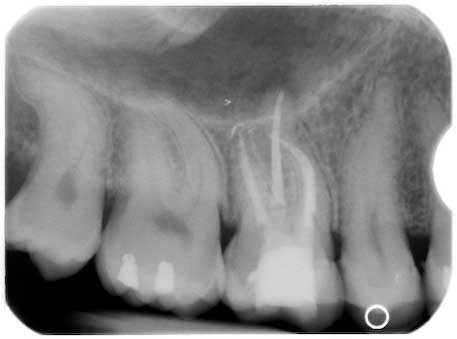

Koryphäenkiller einmal anders